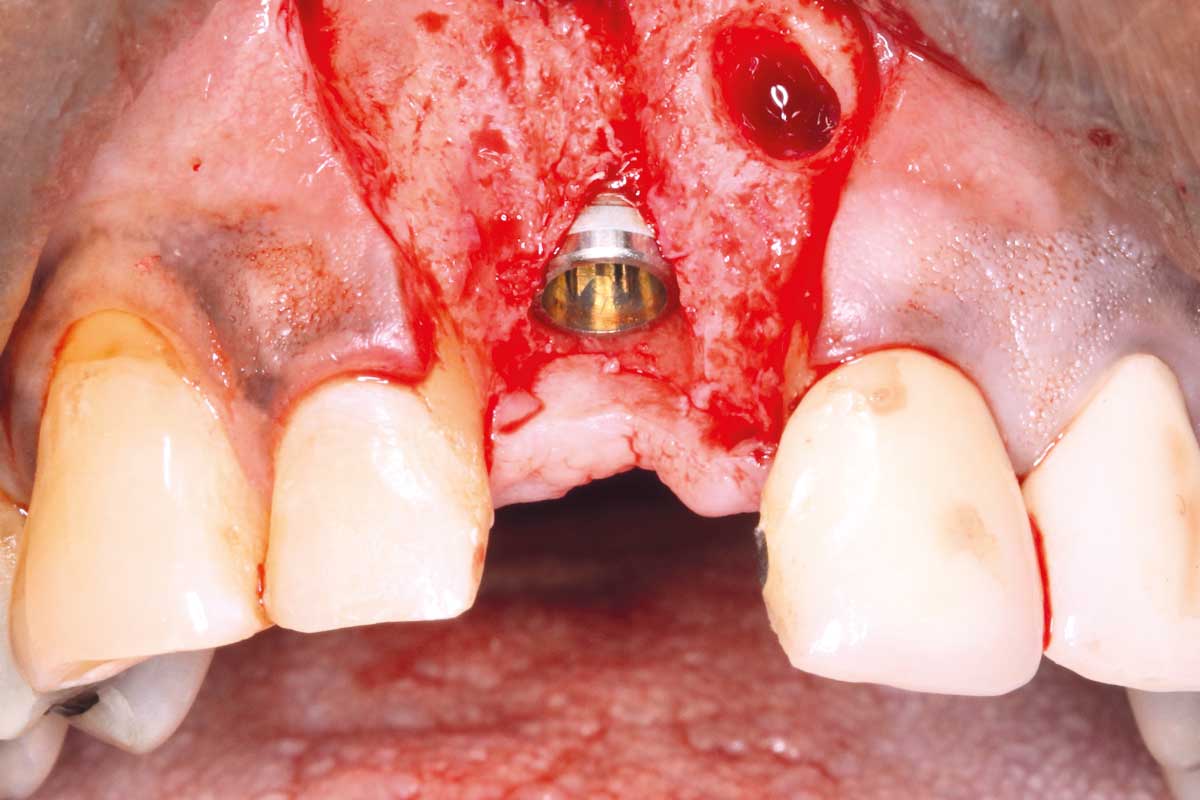

Implant placement and bone augmentation in the aesthetic zone using maxgraft® and permamem® - Dr. A. Puišys

Implant placed in the deficient site. permamem® in place for covering.